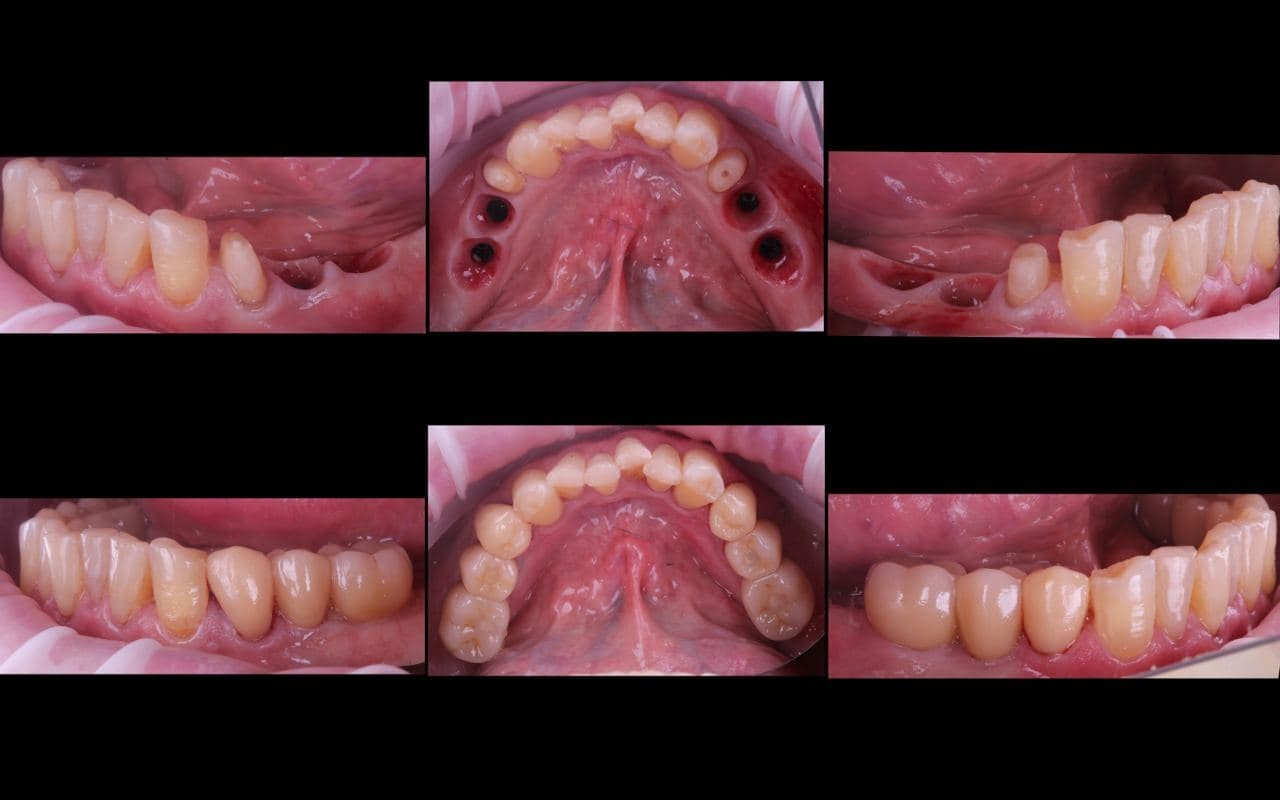

1. Пациент приходит на консультацию. Точнее, его приводит сын, потому что, похоже, что-то пошло не так с прошлым врачом. Это что-то вообще-то можно заметить невооружённым взглядом, но сын далеко не дантист. Но в целом он способен понять, что пеньки зубов с торчащими из них странными штуками — это не очень здоровая ситуация. В руках у пациента — коронки, которые отвалились буквально недавно. Итого восемь пеньков на верхней челюсти и несколько сохранившихся зубов на нижней. Визуально зубов нет, внутри кости есть разрушенные корни, сверху — культяшечки, на которые пытались приклеить конструкцию.

6. Следующим утром пациент приходит, засыпает в кресле под присмотром анестезиолога, мы удаляем все верхние зубы, прикладываем навигационный шаблон, вкручиваем заранее спроектированные импланты в места по шаблону, насыпаем графт экзогенной костной ткани вокруг двух участков, фиксируем ткани и ставим сверху временную конструкцию.

7. Будим пациента, он сидит в кресле, ничего не понимает, но улыбается и трогает пальцем новые зубы.